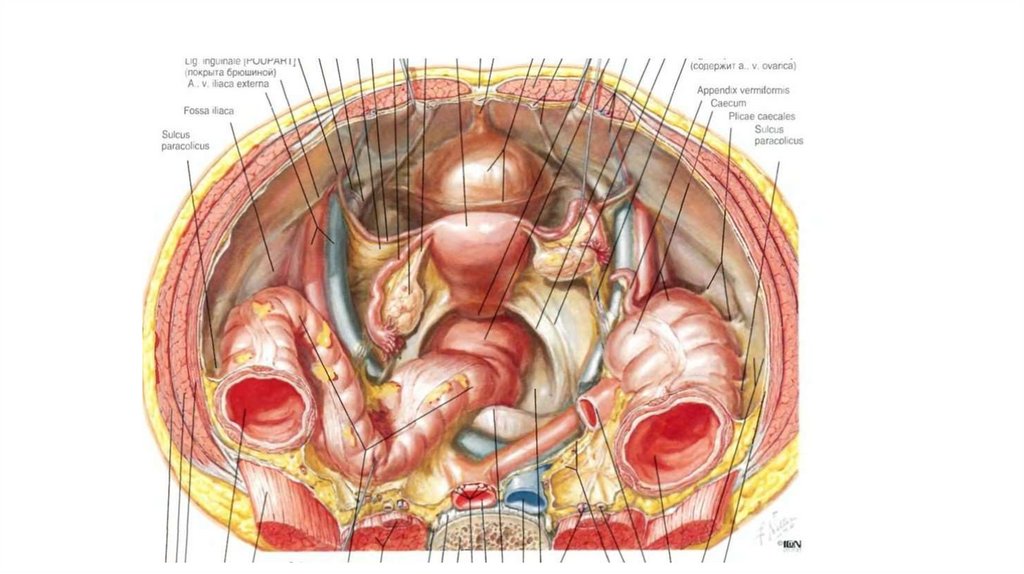

Анатомия малого таза: детальные схемы и изображения